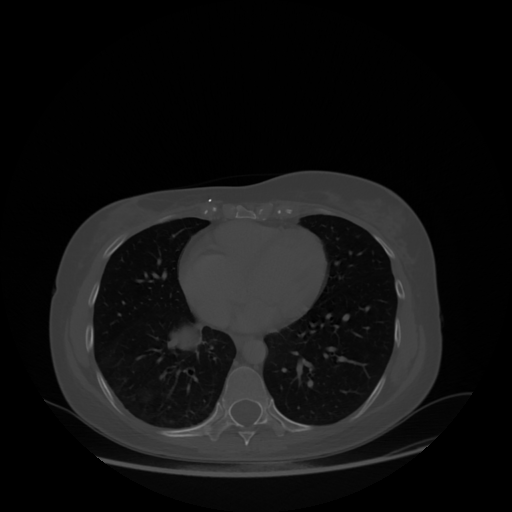

Image Grid

4Γ—3 grid: Rows show different image types (Original NATIVE, Reconstructed NATIVE, Original VENOUS, Generated VENOUS), Columns show windowing techniques (No Window, Lung Window, Mediastinum Window)

Original VENOUS CT scan

Lung window (WL -600, WW 1500 β†’ Low βˆ’1350, High +150)

Generated VENOUS CT scan (A→B translation)